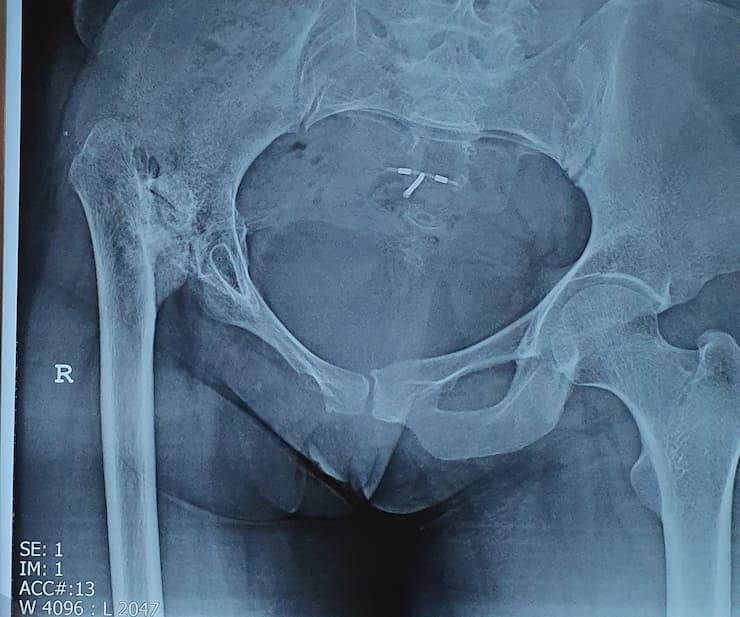

Түнхний үений төрөлхийн мултрал дутуу хөгжилтэй өвчтөний мэс заслын өмнөх болон дараах рентген зураг

Түнхний үе бүтэн солих мэс засал (THA) image3Түнхний үе бүтэн солих мэс засал (THA) image4